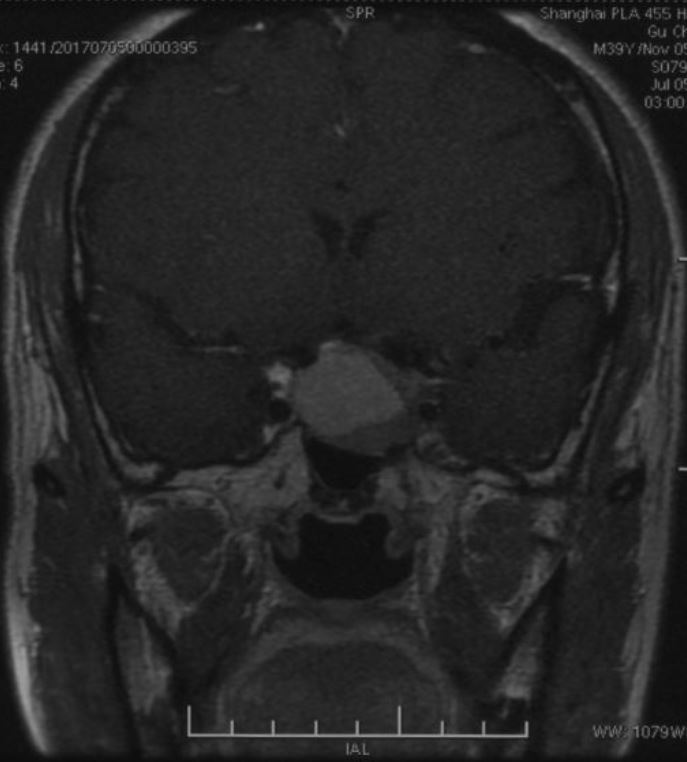

鞍区磁共振检查发现:鞍区肿瘤卒中可能,肿瘤侵犯双侧海绵窦、颈内动脉,鞍隔被顶起,鞍底部分塌陷。

冠状位增强